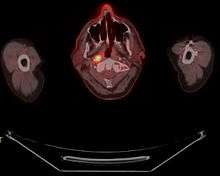

Staging

Staging of nasopharyngeal carcinoma is based on clinical and radiologic examination. Most patients present with Stage III or IV disease.

Stage I is a small tumor confined to nasopharynx.

Stage II is a tumor extending in the local area, or that with any evidence of limited neck (nodal) disease.

Stage III is a large tumor with or without neck disease, or a tumor with bilateral neck disease.

Stage IV is a large tumor involving intracranial or infratemporal regions, an extensive neck disease, and/or any distant metastasis. [10]

Stage T1 nasopharyngeal cancer

Stage T2 nasopharyngeal cancer

Stage T3 nasopharyngeal cancer

Stage T4 nasopharyngeal cancer